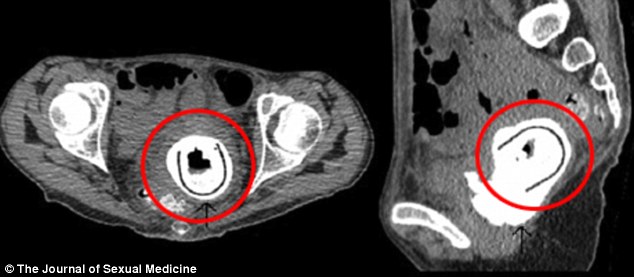

Medicii au fost şocaţi să descopere în vaginul femeii o formaţiune străină corpului care pătrundea din vagin în vezica urinară. După intervenţia de extragere a obiectului din vaginul acesteia s-a constatat că era vorba de o jucărie sexuală de 11 cm lungime.